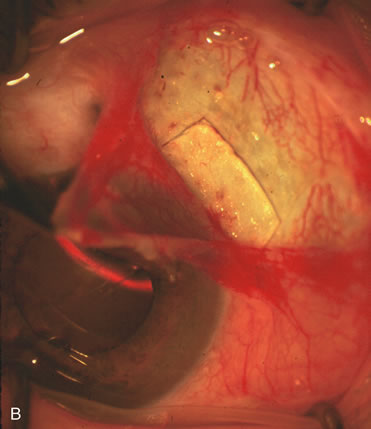

Fig. 7. Phacotrabeculectomy adjacent to a failed filter in cataractous eye. The ability to combine small-incision cataract extraction with trabeculectomy all through the same incision adjacent to the failed filter allows the surgeon to work in a familiar superior area. Avoiding incisions into the existing bleb decreases conjunctival buttonholes, hypotony, operating room time, and subconjunctival bleeding. A. Appearance of failed bleb with exposure of superior temporal quadrant gained with a corneal traction suture. B. Prepare a limbus-based conjunctival flap and a scleral flap. C. This bleb is at high risk to fail again justifying the need for MMC, 0.2 mg/cc applied on a pledget for 4 minutes. D. Insert the keratome and perform phacotrabeculectomy in the usual fashion.

The inflammation associated with lens extraction at any site usually causes complete failure of a marginal functioning bleb. In addition, pressure reduction by medical means is usually minimal in these recalcitrant cases, and combined surgery is indicated. In the past, these cases were approached with large-incision ECCE, clear corneal cataract incision, and bleb revision. Drawbacks included those mentioned earlier for large incision clear corneal cataract extraction, and bleb revision is often associated with conjunctival buttonholes, wound leaks, subconjunctival hematoma, destruction of friable sclera, and associated hypotony. With the advent of modern-day cataract surgery, a phacotrabeculectomy is often possible adjacent to the failed filter (Fig. 7). The ability to combine cataract extraction with implant and filtration surgery all through the same small incision has greatly improved outcomes for patients with marginal preoperative filters. There are several other viable options in this case. If the surgeon elects to remove the cataract through a temporal clear corneal incision, the bleb may be revised or a new adjacent filter fashioned. As mentioned earlier, revising a failed filter is technically challenging. If the surgeon believes it is not feasible to revise the filter or fashion a new one, a glaucoma drainage implant is a reasonable option combined with temporal lens extraction.172